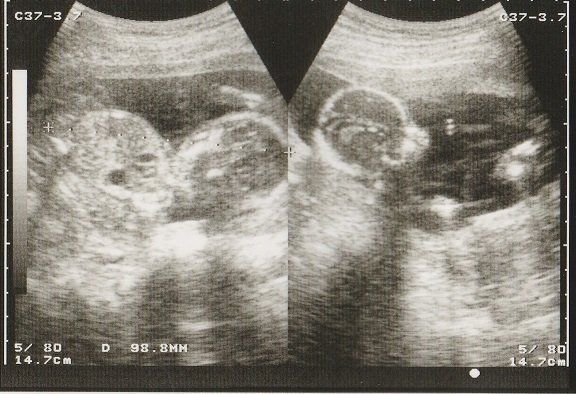

妊娠30週目のエコー写真 お母さんも大きくなる時期

赤ちゃんも順調に育っていますが、お母さんの体重も増え気味に…。「あまり体重が増えると管理入院ですよ」と、看護婦さんに釘を刺されました。

妊娠32週目のエコー写真 おなかもぱんぱんです。

AC(おなかの周囲の長さ)などから、赤ちゃんの推定体重を計算するようです。赤ちゃんのおなかも大きくなっていますが、お母さんのおなかもぱんぱんです。